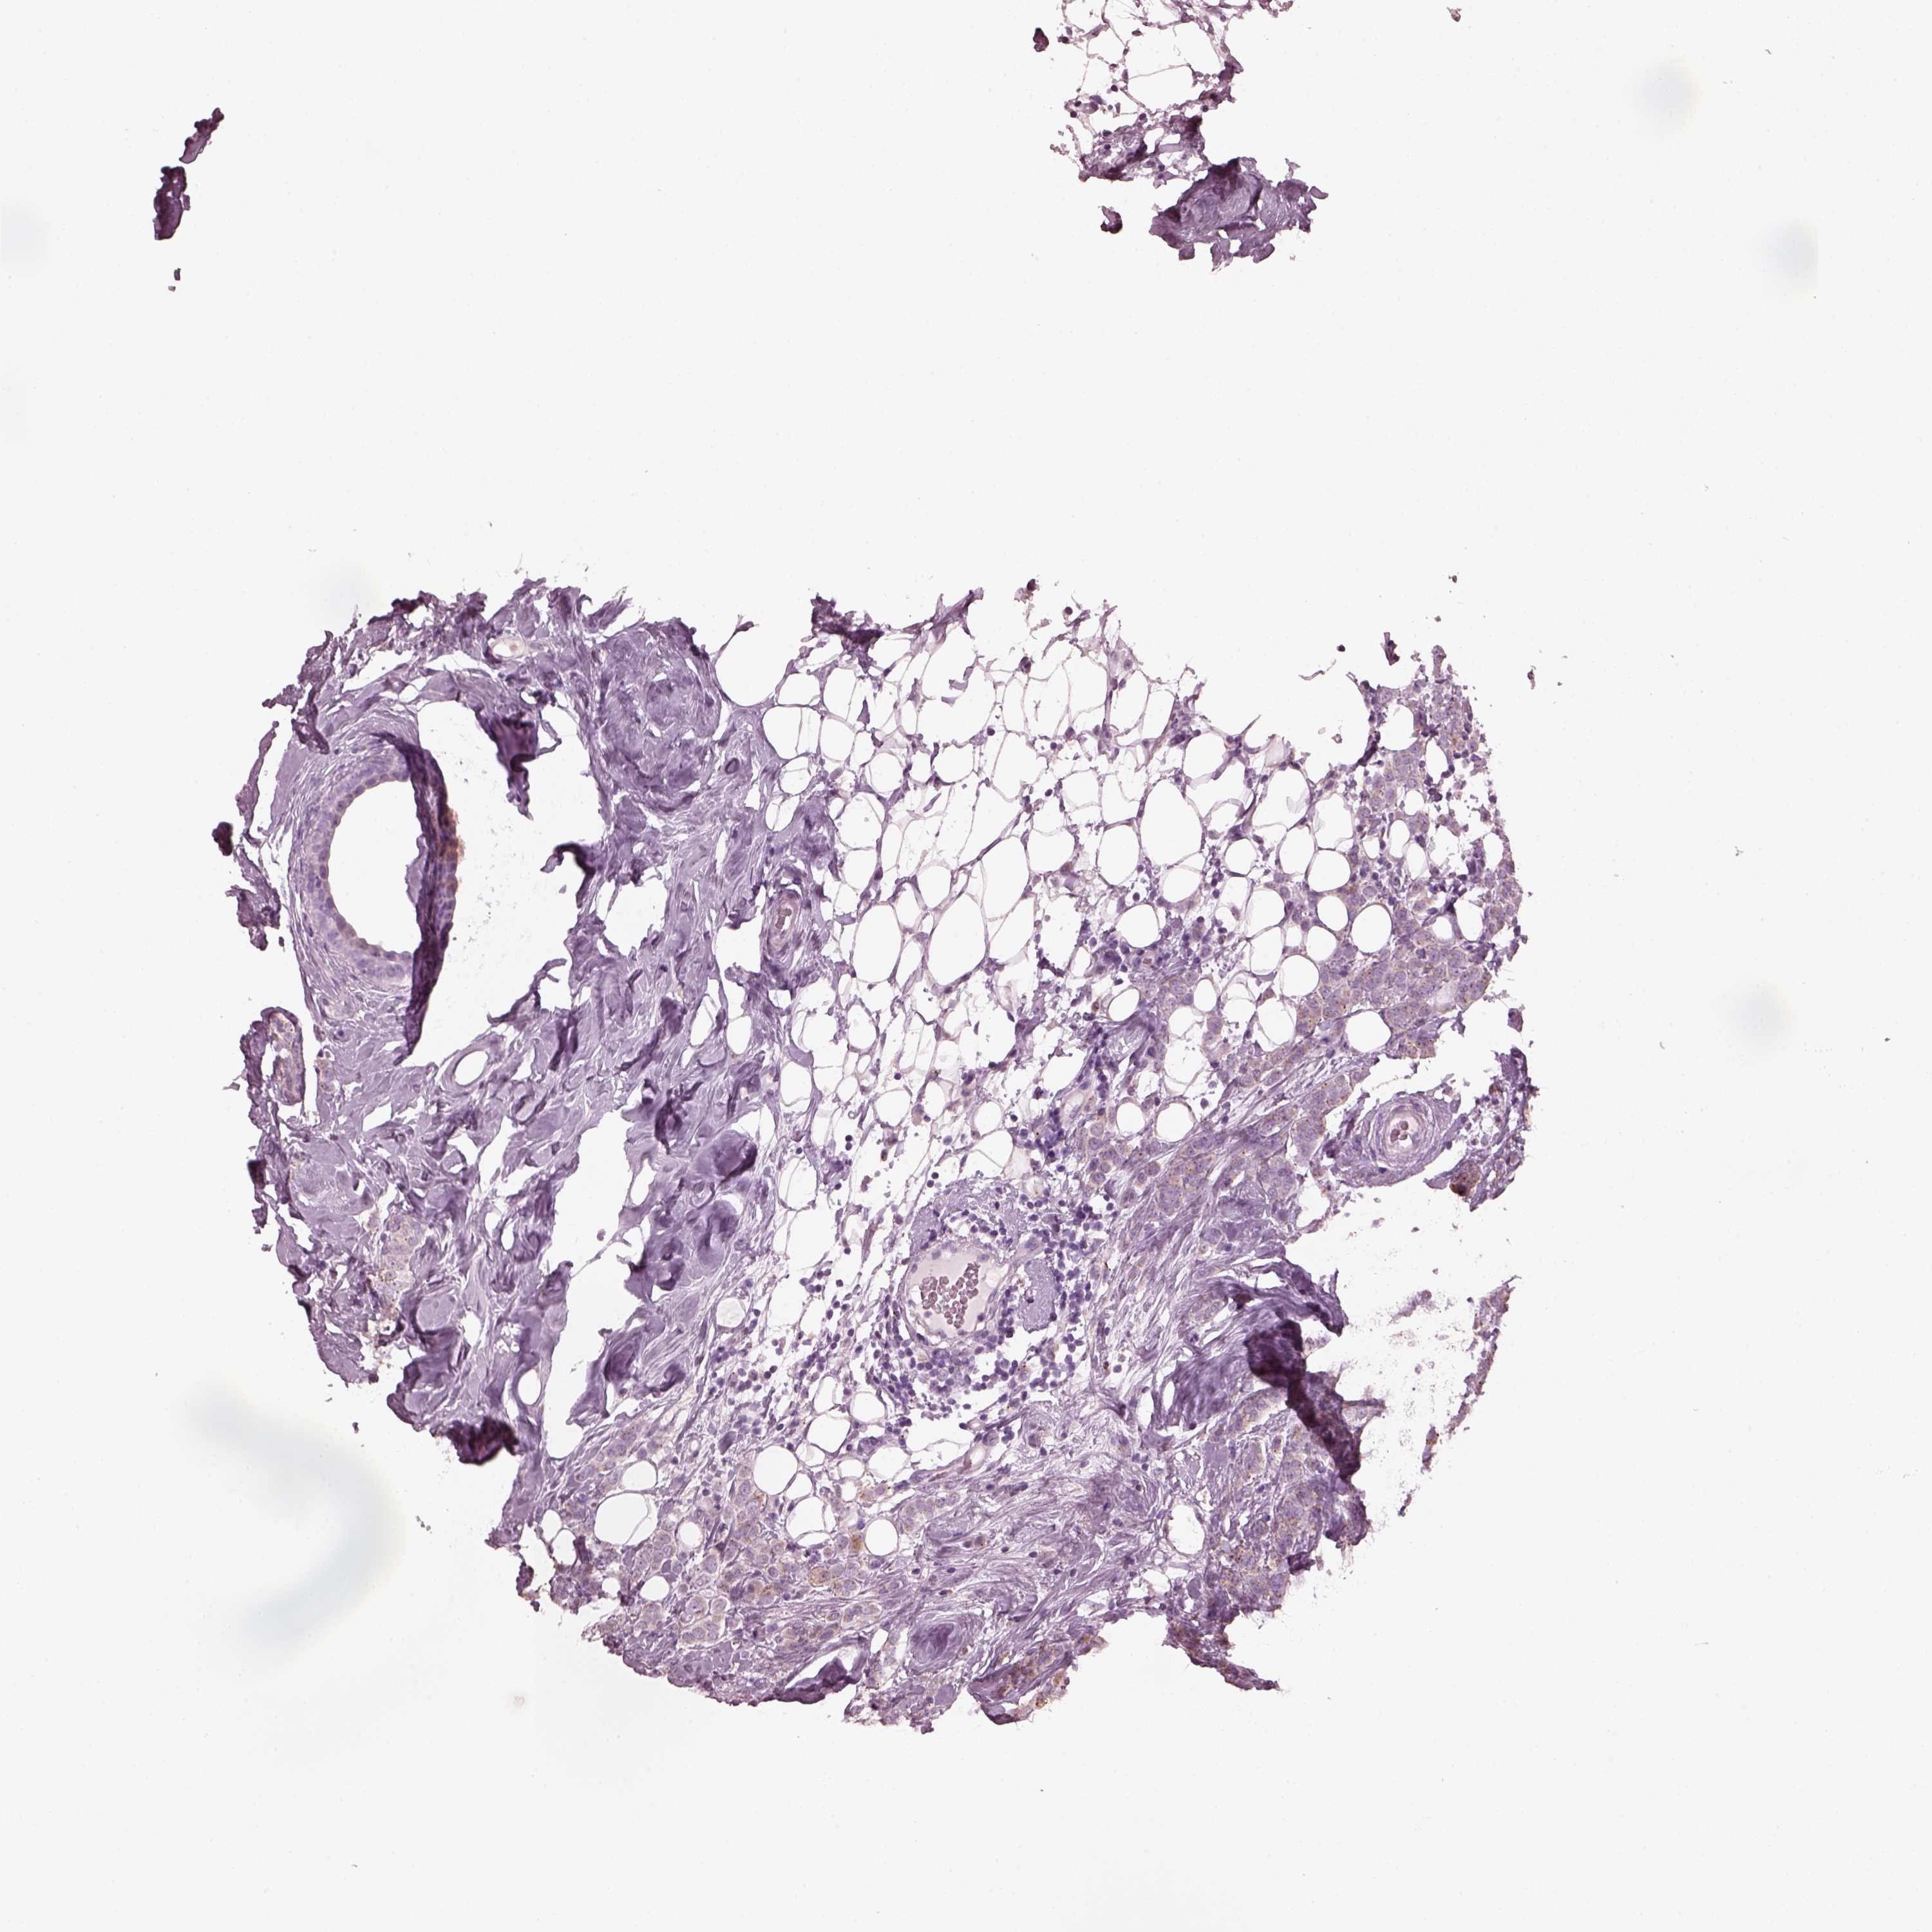

CANCER BREAST CANCER Show tissue menu

BRCA TCGA BRCA VALIDATION PROTEIN EXPRESSION

Breast cancer

Human cancer